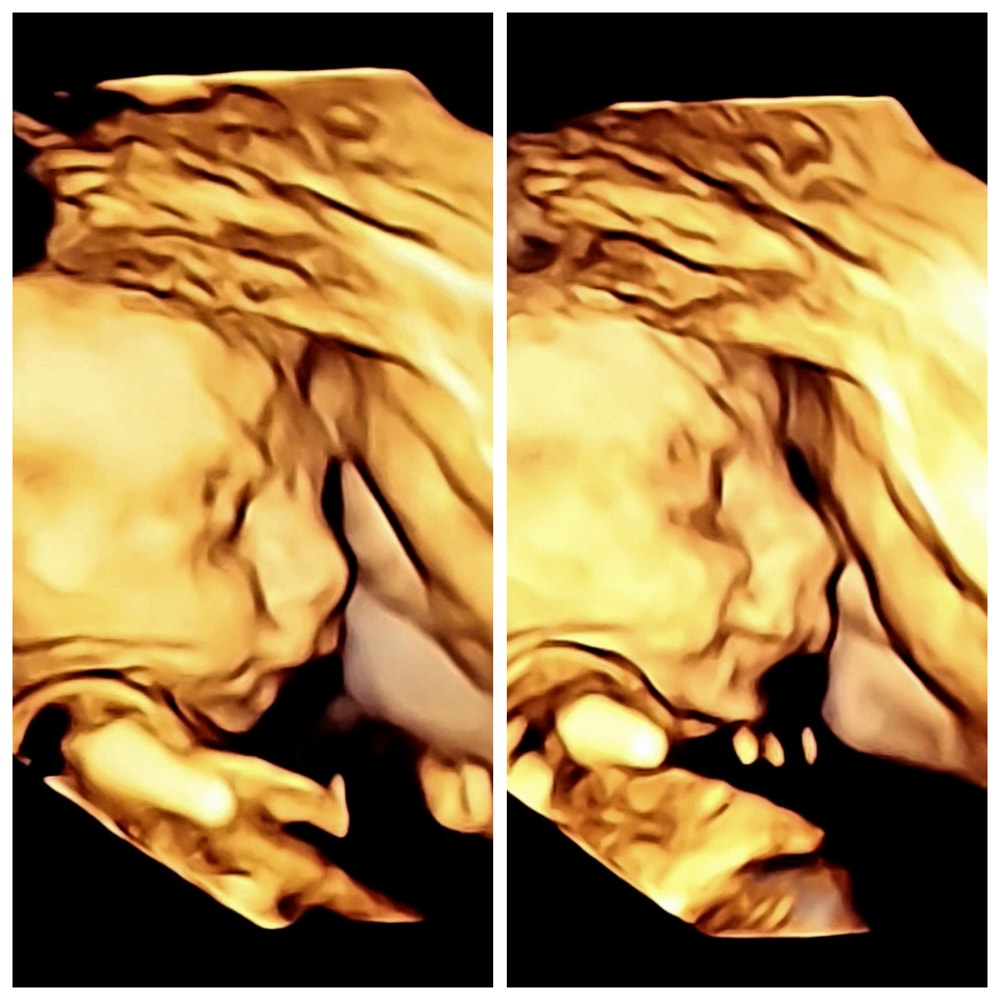

Теперь даже по профилю можно сказать, что он - вылитый муж. Нос, конечно, ещё изменится, но характерный изгиб уже виден 🥹

Ну и самый трогательный материнский момент для меня: сын не любит УЗИ, пытается закрыться, но в этот раз я стала ворковать с ним, уговаривая сделать фото для бабушек и дедушек. И он перестал отворачиваться и... улыбнулся 🥹🥹🥹